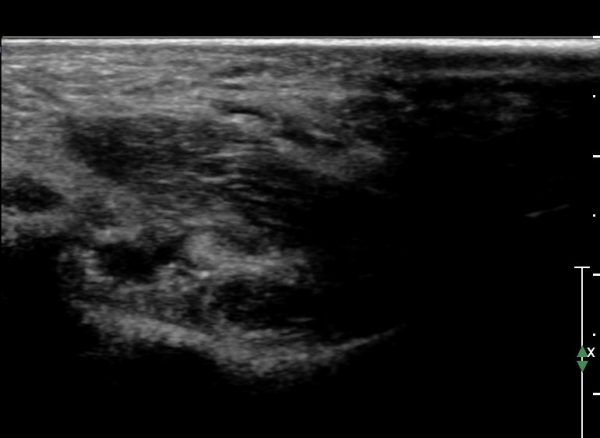

Å½ÃËÀÚ¸¦ Á¶±Ý ¸»´ÜÀ¸·Î À̵¿ÇÏ´Ï Èİæ°ñ ½Å°æÀÌ ³»Ãø Á·Àú½Å°æ°ú ¿ÜÃø Á·Àú ½Å°æÀ¸·Î ³ª´©¾îÁü(»çÁø 2)